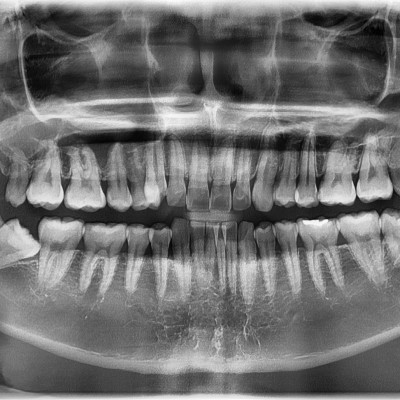

#28,38,48 사랑니 발치 #28,38,48 사랑니 발치 구강 외과 전문의가 당일 발치했습니다.